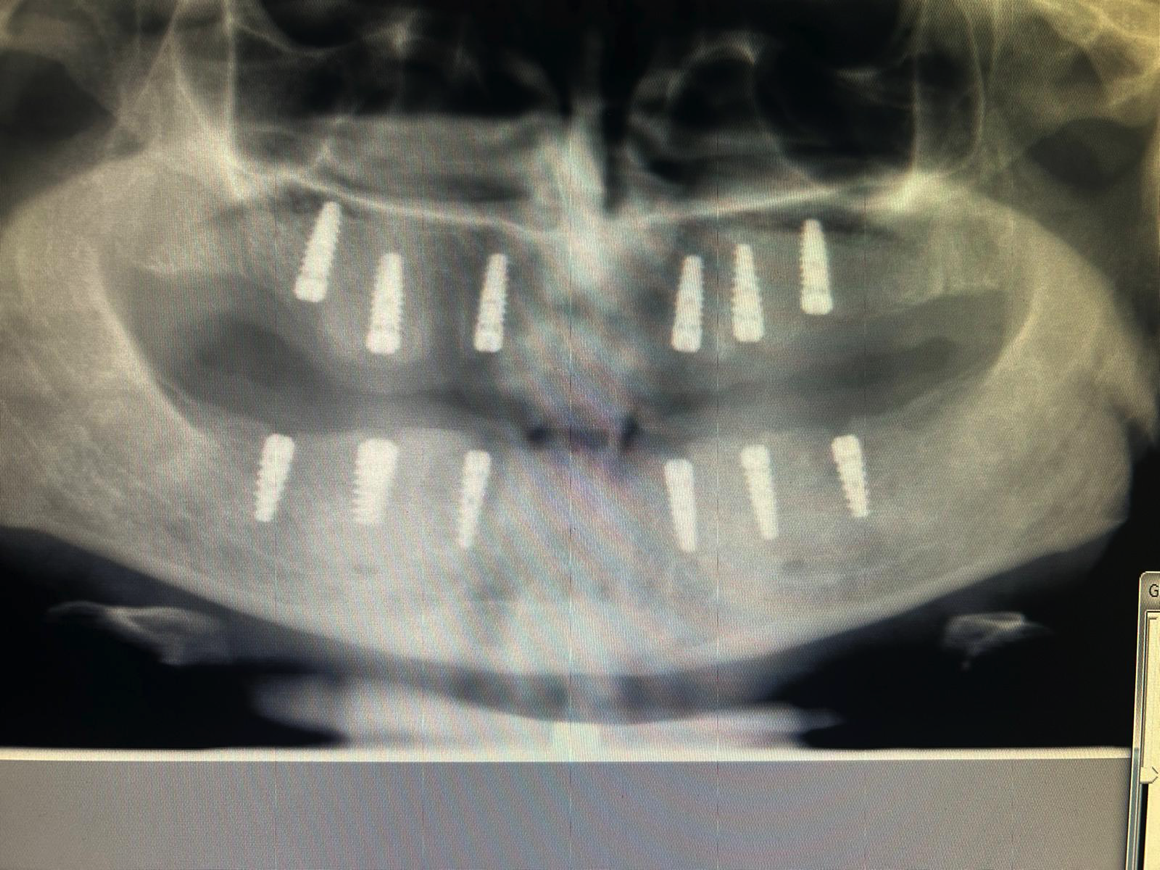

Görselde gördüğümüz o agresif çift sarmal yapı, implantın kemiğe travma yaratmadan, kontrollü ve hızlı bir şekilde yerleşmesini sağlar. Her türlü kemik yoğunluğunda (Tip 1'den Tip 4'e kadar) mükemmel primer stabilite.

Gövde boyunca uzanan çift girişli yiv tasarımı, yerleştirme sırasında kemiği travmatize etmeden aktif bir tutunma sağlar.Özellikle yumuşak kemik tiplerinde bile üst düzey primer stabilite sunarak, "Hemen Yükleme" (Immediate Loading) protokolleri için güvenli bir zemin hazırlar..

Agresif çift girişli yiv geometrisi, implantın kemik içine travma yaratmadan, kontrollü bir şekilde ilerlemesini sağlar. En yumuşak kemik tiplerinde bile üstün primer stabilite ve hemen yükleme (immediate loading) imkanı.